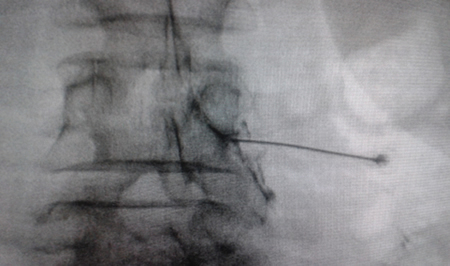

El acceso por vía transforaminal es el más utilizado (4). Se coloca al paciente en decúbito prono con una almohada a nivel abdominal para revertir la lordosis fisiológica. Las agujas o cánulas de radiofrecuencia que utilizamos con más frecuencia son de diámetro 20 o 22 G de 98 mm de largo con punta activa de 0,5 o 1 cm. Después de la asepsia con clorhexidina alcohólica y la colocación de campos estériles, se realizan enfoques radiológicos en incidencia anteroposterior, oblicuo y lateral. En incidencia anteroposterior y moviendo el arco en dirección cráneo caudal se borra el doble arco del borde inferior vertebral. En incidencia oblicua entre 20 y 30 grados ipsilateral al GRD a tratar, se visualizará la clásica imagen descrita como de “Scotty Dog”, que es resultado de acercar el macizo facetario y la apófisis espinosa al lado contralateral. El punto de entrada será entonces inmediatamente debajo del pedículo. Previa anestesia local con lidocaína al 1 %, la aguja se introducirá siguiendo una visión túnel y no se avanzará más allá de la mitad del pedículo en esta proyección con la finalidad de prevenir la lesión neural. En proyección lateral, se introducirá en el techo del neuroforamen

(Figuras 1 y 2) pero la localización final será determinada por la estimulación nerviosa sensitivo-motora. La estimulación sensitiva consiste en provocar parestesia o dolor en el territorio afectado con una estimulación entre 0,3-0,6 v. Durante la estimulación motora se pueden provocar fasciculaciones en el territorio afectado con un voltaje del doble al necesario para provocar las parestesias. Si se desea realizar una denervación intraganglionar, promulgada por algunos autores, la estimulación tanto sensorial como motora será positiva a menos de 0,3 v. Por tratarse de un procedimiento más doloroso, se aconseja administrar anestésicos locales después del estímulo doloroso y antes de realizar el tratamiento. La impedancia deberá mantenerse por debajo de 450 ohms, lo que se consigue infundiendo solución salina previa a la RF (4). La utilización de contraste constituye una buena práctica, ya que descarta la posición intravascular e intratecal de la cánula de radiofrecuencia.

Fig. 2. Imagen radiológica anteroposterior de una cánula de radiofrecuencia posicionada en neuroforamen L4-L5, en el llamado triángulo de seguridad, después de la inyección de contraste. Se observa un engrosamiento del radiculograma a nivel del techo del neuroforamen, que podría corresponder al ganglio de la raíz dorsal de L4